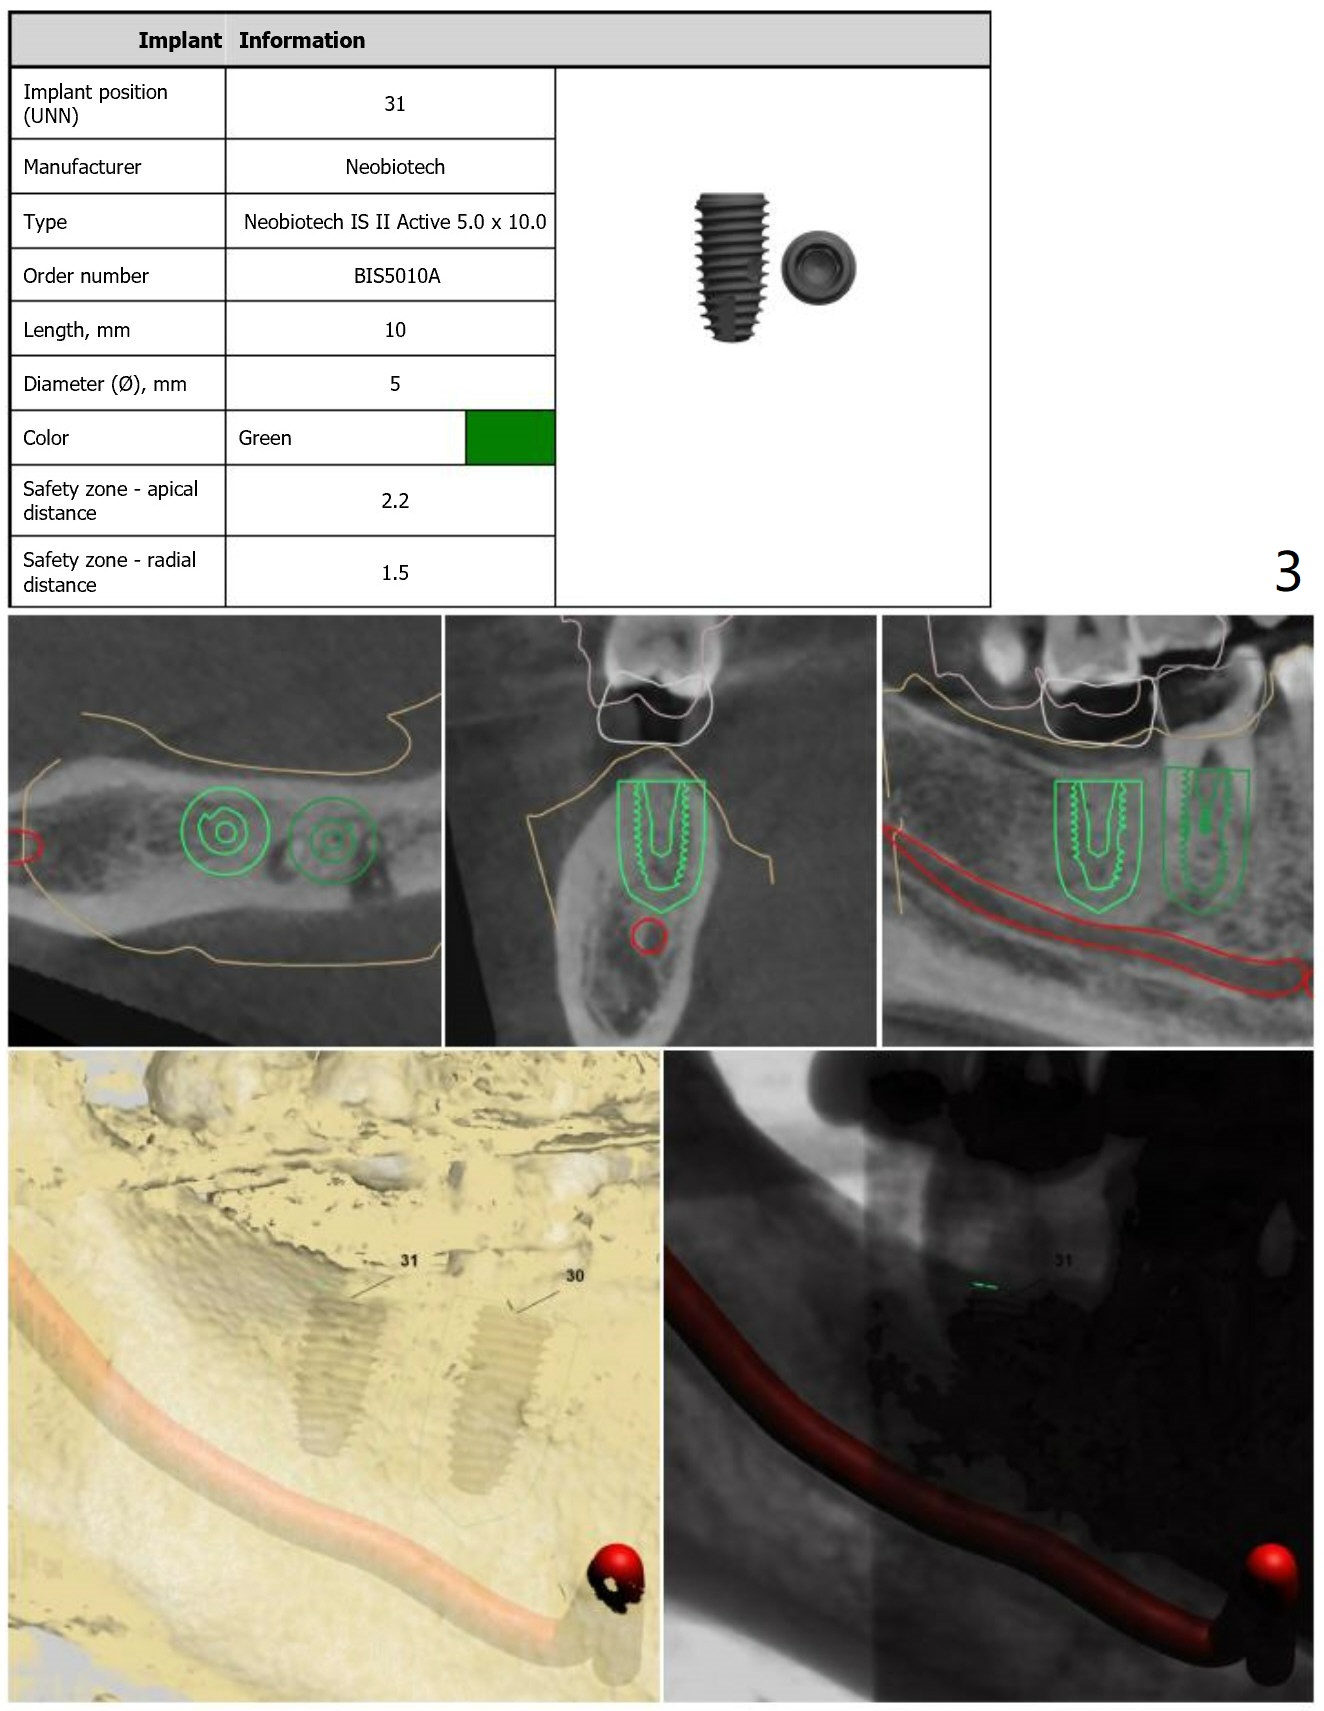

Return to Lower Molar Immediate Implant, Prevent Molar Periimplantitis (Protocols, Table), Trajectory, Clindamycin Xin Wei, DDS, PhD, MS 1st edition 11/30/2018, last revision 01/15/2019